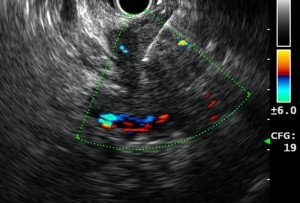

Endoscopic ultrasound (EUS) is an advanced endoscopic procedure specialized for the evaluation of various benign and malignant diseases involving the gastrointestinal tract and pancreatobiliary system using an ultrasound probe equipped on a flexible endoscope. Depending on the disease condition being evaluated, an EUS procedure usually takes about 20 to 40 minutes. Common conditions that can benefit from EUS are listed below (Table 1).

With its high resolution imaging, EUS can provide important information for local staging in patients with suspected gastrointestinal or pancreatobiliary tumours. When histological diagnosis is needed, EUS guided Fine Needle Aspiration (EUS-FNA) is a valuable technique for specimen acquisition. In addition to diagnostic evaluation, EUS can also be therapeutic. For example, in patients with chronic pain from pancreatic cancer, EUS guided Celiac Plexus Neurolysis (EUS-CPN) can provide effective palliation of cancer related pain, improving quality of life.

- EUS guided Celiac Plexus Neurolysis for pancreatic cancer pain control